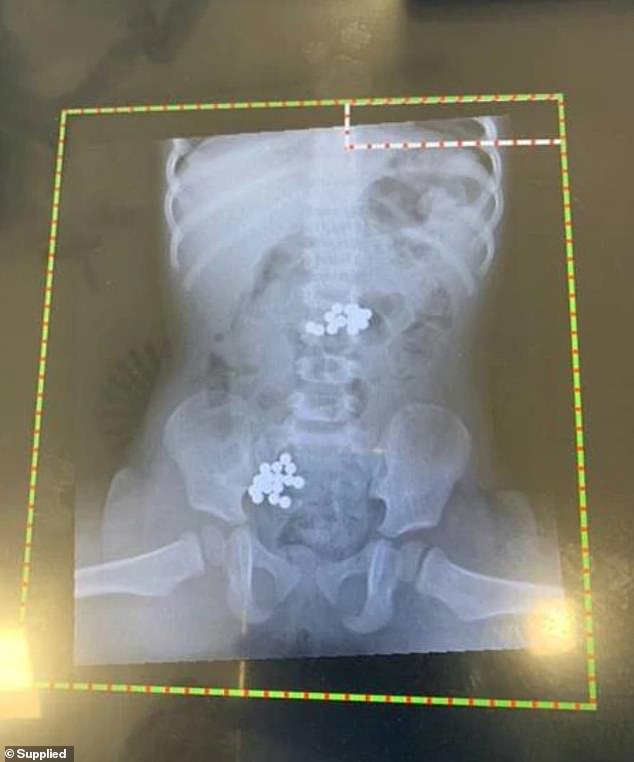

将女儿送医后,布朗说:“医生给她做了X光检查,发现她的胃部和肠子里有32个磁铁滚珠。”此外,经检查医生还发现小女孩的姐姐也吞下了两个磁铁滚珠。